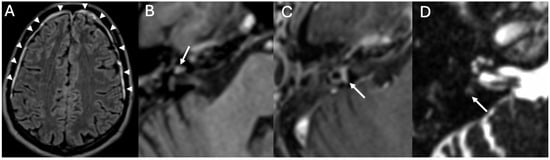

3.1. Otomastoiditis

3.1.1. Imaging

| Otomastoiditis and Otogenic Meningitis | Saat et al., 2015 [17]; Rubini et al., 2024 [18]; Vazquez et al., 2003 [19]; Bruschini et al., 2017 [20]; Barry et al., 2019 [21] | Retrospective studies, imaging reviews, and case reports | HRCT and MRI identify middle ear/mastoid infection and intracranial spread; meningitis occurs in up to 35–46% of untreated cases. |